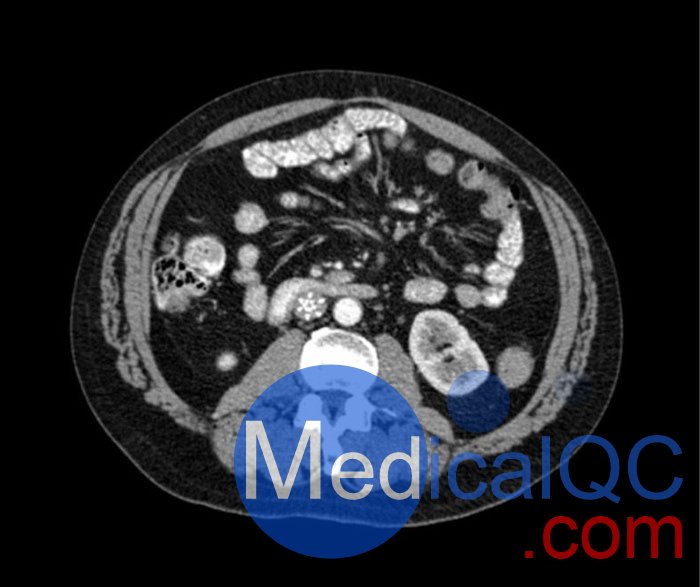

WEK53-04肝硬化腹部模體,WEK53-04腹部模體代表膽囊切除術(shù)后的腹部,帶有小夾子。肝臟有肝硬化的典型體征,在第三腰椎水平植入下腔靜脈過濾器。兩個腎臟都有囊性病變,左側(cè)有一小塊腎結(jié)石。

• 下腔靜脈濾器

• 腎囊腫

• 腎結(jié)石

• 淋巴結(jié)腫大